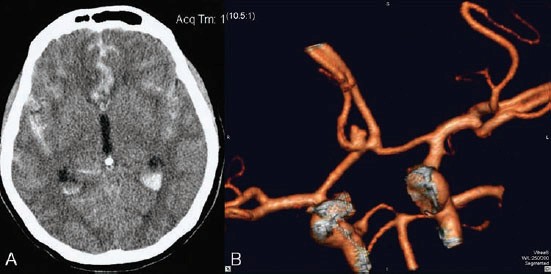

A CT scan of the head is usually the first test and often shows the bleeding.

CT angiogram – a CT scan with contrast dye to look at blood vessels

The most common cause of spontaneous subarachnoid haemorrhage is rupture of a brain aneurysm.

An aneurysm is a weak area in the wall of a blood vessel that can slowly bulge and eventually burst, causing bleeding.